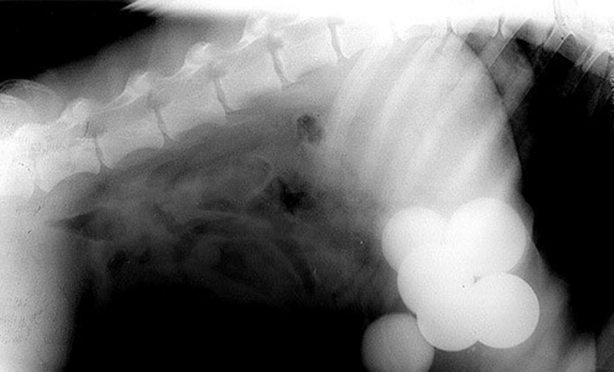

Hamile bir kedi ve onun röntgen filmi.

#2